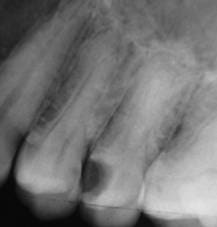

Les radios montrent quand même une image significative en distal de 24 et mésial de 26 , de visu ce peut être différent.

La dernière radio montre un traitement canalaire bien effectué.

Y'a quand même clairement une carie sur la 6, pas gigantesque d'accord mais elle est bien là, on est plusieurs à te le dire et pourtant tu persistes à répondre que non.